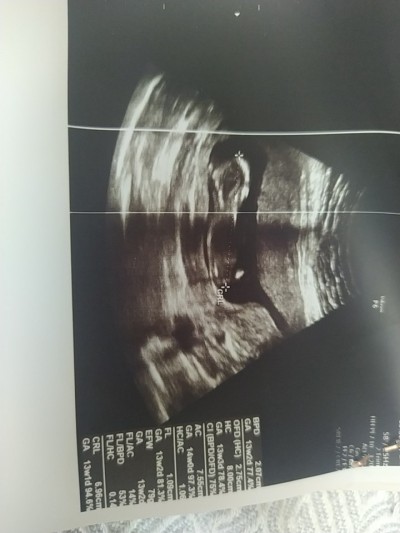

Gebelik haftası

13+0

Kız gibi sanki canım saglicakla al kucağına yanlız burada bu sorular sorulmuyor sohbet bölümünde soruluyor bu bölümde yasak kapatırlar sorunu canım